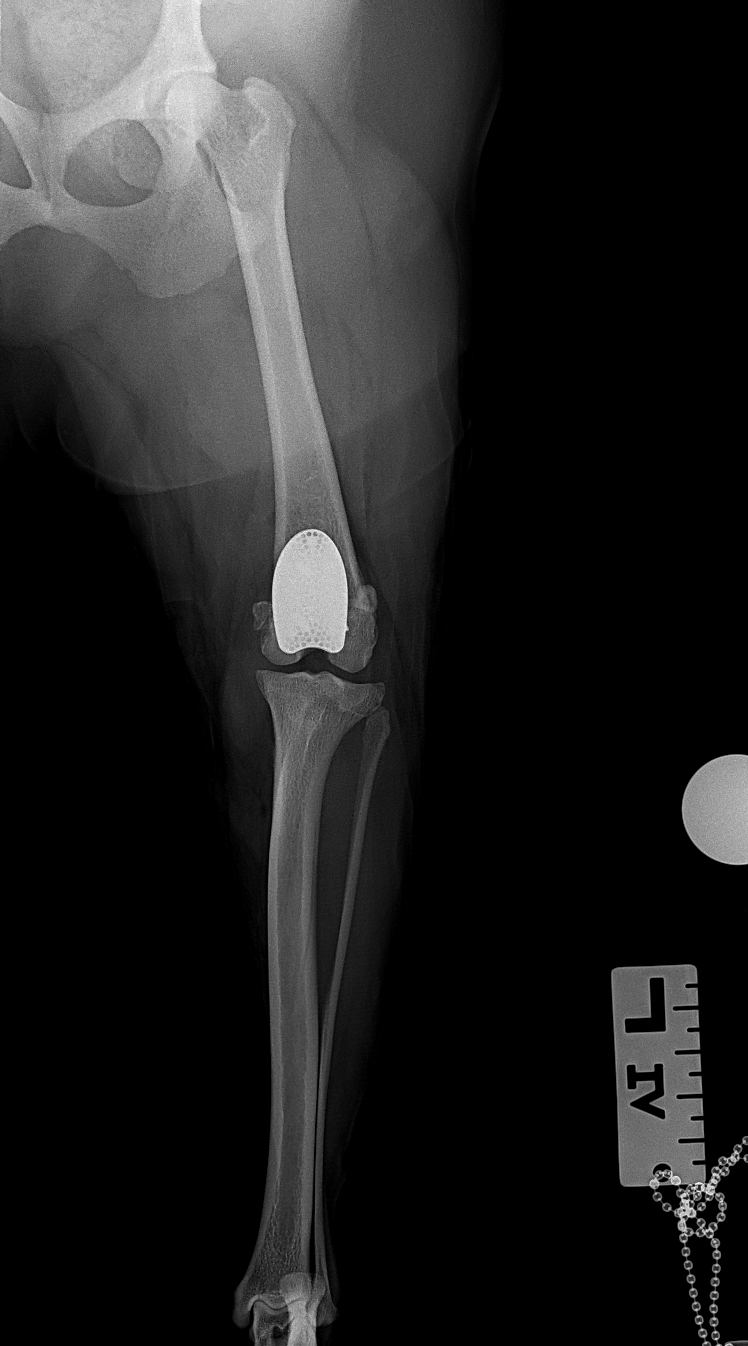

膝蓋骨内方脱臼に伴い慢性の異常な刺激が進行し、骨関節炎を認め関節軟骨はすでに不可逆的な変性を呈しています。多くの外科手術は”整復”を目的としますが、関節炎が進行した関節においては、単なる整復だけでは痛みや機能障害は残り続けます。そこで必要な手技は”再建”です。損傷した関節面をそのまま使うのではなく、人工滑車(PGR)を用いて新たな滑走面(DLC)を構築することで、関節内の異常なストレスを減少させ、除痛と機能回復を図ります。HAコーティングのベースプレートと骨がオッセオ・インテグレーションを起こすまでは安静が必要です。